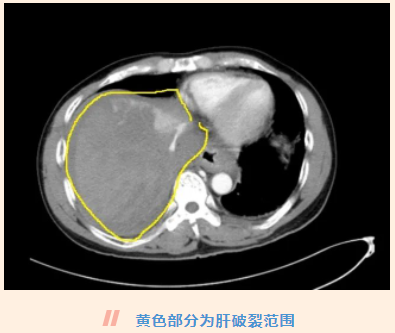

来到医院后,急诊检查发现钟叔肝脏破裂范围非常大且深,门静脉、肝右静脉、肝中静脉等肝内主要大血管全部严重损伤。此外,还有右肾挫裂出血、血气胸、多发骨折等。眼下钟叔因肝脏持续大出血,失血过多,已经出现休克,手术是唯一的抢救方法。

手术开始后,大量的积血从腹腔涌出,肝脏已经出现“星状”的严重碎裂,范围超过右半肝,约“柚子”大小,多支大血管持续出血,部分肝脏缺血坏死,没有填塞止血及修补复原的可能,只能把碎裂的肝脏切掉才能止血。